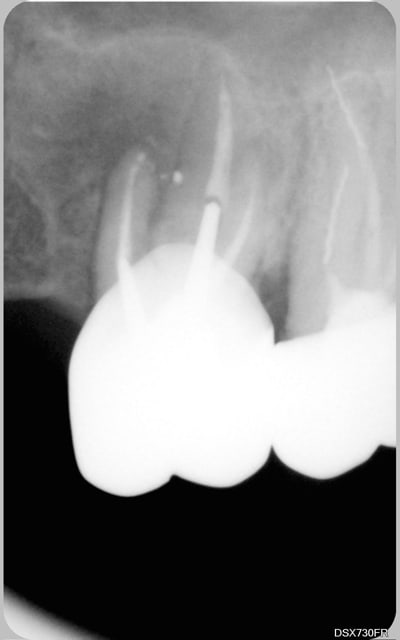

tu veux des images...en voilà 2...avant traitement et 6 mois plus tard...

25 08 2008 fya484 - Eugenol

C'est un beau début de cicatrisation.

Un début de guérison c'est léger pour un fil lu 1463 fois.

Toi, pour commencer, t'as bien une image de guérison complête !!!!!

Un exemple parmis d'autres...

2e essai

01   07 avril 2006 qgskan - Eugenol

02  26 mai 2006 obtqtd - Eugenol

03   13 juin 2006 rr1srh - Eugenol

suite

04   26 juin 2006 i64cza - Eugenol

05   17 janvier 2007 efux3r - Eugenol